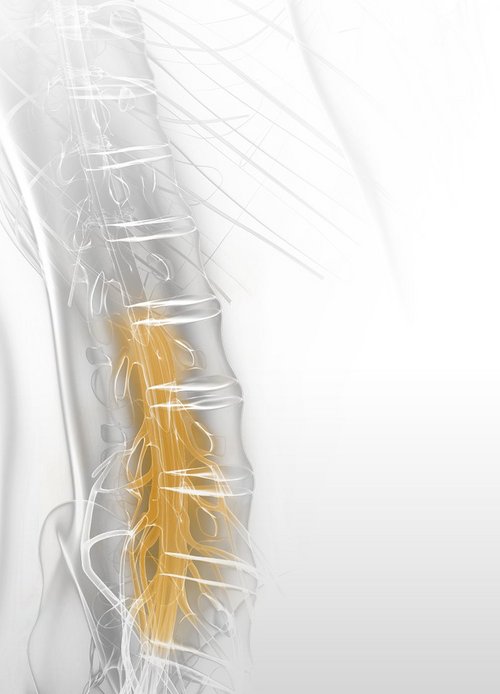

Neural structures within the spine may become compressed by bony or ligamentous tissues within the spinal canal. Categorization based on location of the stenosis is used for differentiating lateral (foramen, lateral recess) and central spinal stenosis.

Central Stenosis

The central stenosis involves compression of the spinal cord and nerve roots. Symptoms can be central or radicular. Surgical treatment includes resecting impinging bone and the ligamentum flavum via an ipsilateral full-endoscopic interlaminar approach, extending to the contralateral side when necessary. The VERTEBRIS X system ensures effective bilateral decompression while preserving non-compressive tissues.